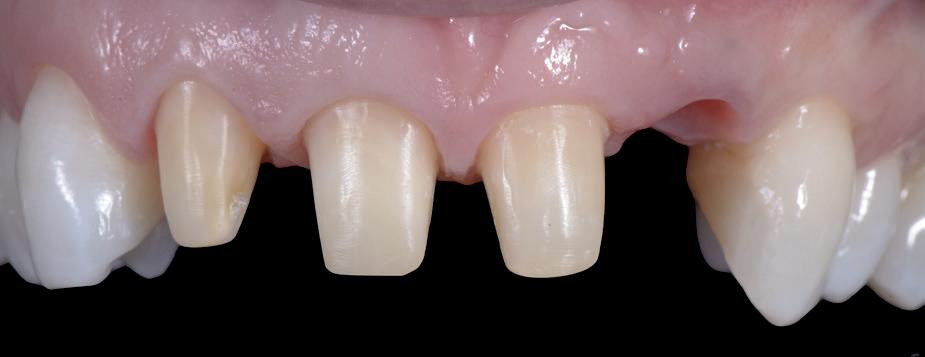

Mevrouw werd naar het Dental Design Center verwezen om een complex probleem aan het bovenfront te beoordelen en indien mogelijk te behandelen. Tien jaar geleden zijn er om esthetische redenen op de 12, 11, 21 en 22 kronen geplaatst. Helaas bleek achteraf een wortelkanaalbehandeling van de 22 noodzakelijk. Na een aantal jaar ontstond er weer een infectie apicaal aan de 22 en werd er een apex uitgevoerd. Helaas had deze behandeling niet het beoogde resultaat. Twee weken voordat ze bij mij op consult kwam, is het element geëxtraheerd en is er een partiële plaat geplaatst als tijdelijke oplossing (foto 1-3).

Na de IPP (esthetisch/functionele) analyse blijkt dat de gezichts- en faciale mediaan niet geheel overeenkomen en dat de gingiva lijnen van het bovenfront niet helemaal parallel lopen met de interpupillaire lijn. Na overleg met mevrouw kiest zij ervoor om dit niet orthodontisch te laten corrigeren. Mevrouw

heeft de nadrukkelijke wens om geen brugconstructie te krijgen. Om die reden is een etsbrug of een conventionele brug geen optie. Daarom bestaat het behandelvoorstel uit vier losse kronen waarvan de 22 implantaat gedragen zal zijn. Een gedetailleerd onderzoek van de regio 22 is noodzakelijk (foto 4-6).

Uit het röntgenonderzoek blijkt dat op de locatie van de 22 veel bot verloren is gegaan en dat er niet direct een implantaat geplaatst kan worden. Om die reden is een botaugmentatie geïndiceerd. Wel zijn distaal van de 21 en mesiaal van de 23 de botpieken aanwezig die de papillen ondersteunen. Naast te weinig bot, is op de locatie 22 in bucco-linguale richting ook te weinig volume gingiva aanwezig. Daarom zal er tevens een soft tissue graft aangebracht worden. Tijdens deze behandeling wordt ook de recessie op de 23 zoveel mogelijk bedekt (foto 7 en 8).

Het botdefect wordt geaugmenteerd met een allograft (Biohorizons MinerOss A). Om dit volume te stabiliseren, wordt een titanium versterkt membraan aangebracht (Cytoplast ti-reinforced d-PTFE membraan) met daaroverheen een collageen membraan (Mem-Lok collagen matrix). Na sluiting van de flap wordt de 4-delige PMMA brug, die al is gefreesd in het laboratorium naar aanleiding van de planning, gerelined en geplaatst met een tijdelijk cement (foto 9-14).

De flap en graft worden met poly-propelene 6.0 hechtingen gefixeerd. De tijdelijke reconstructie wordt herplaatst (foto 17-20).

Na 4-6 weken kan het aangebrachte healing abutment worden vervangen door een tijdelijk abutment. Deze wordt aan de kunststof reconstructie verbonden om zo de gingiva ter plaatse van de 22 te vormen. Zo lijkt het of er geen implantaat maar nog steeds een wortel aanwezig is, wat het esthetisch eindresultaat ten goede zal komen (foto 21-23). Vanaf 4-6 maanden ziet het weefsel er gezond uit. Nu kan met de uiteindelijke restauratiefase worden gestart (foto 24 en 25).